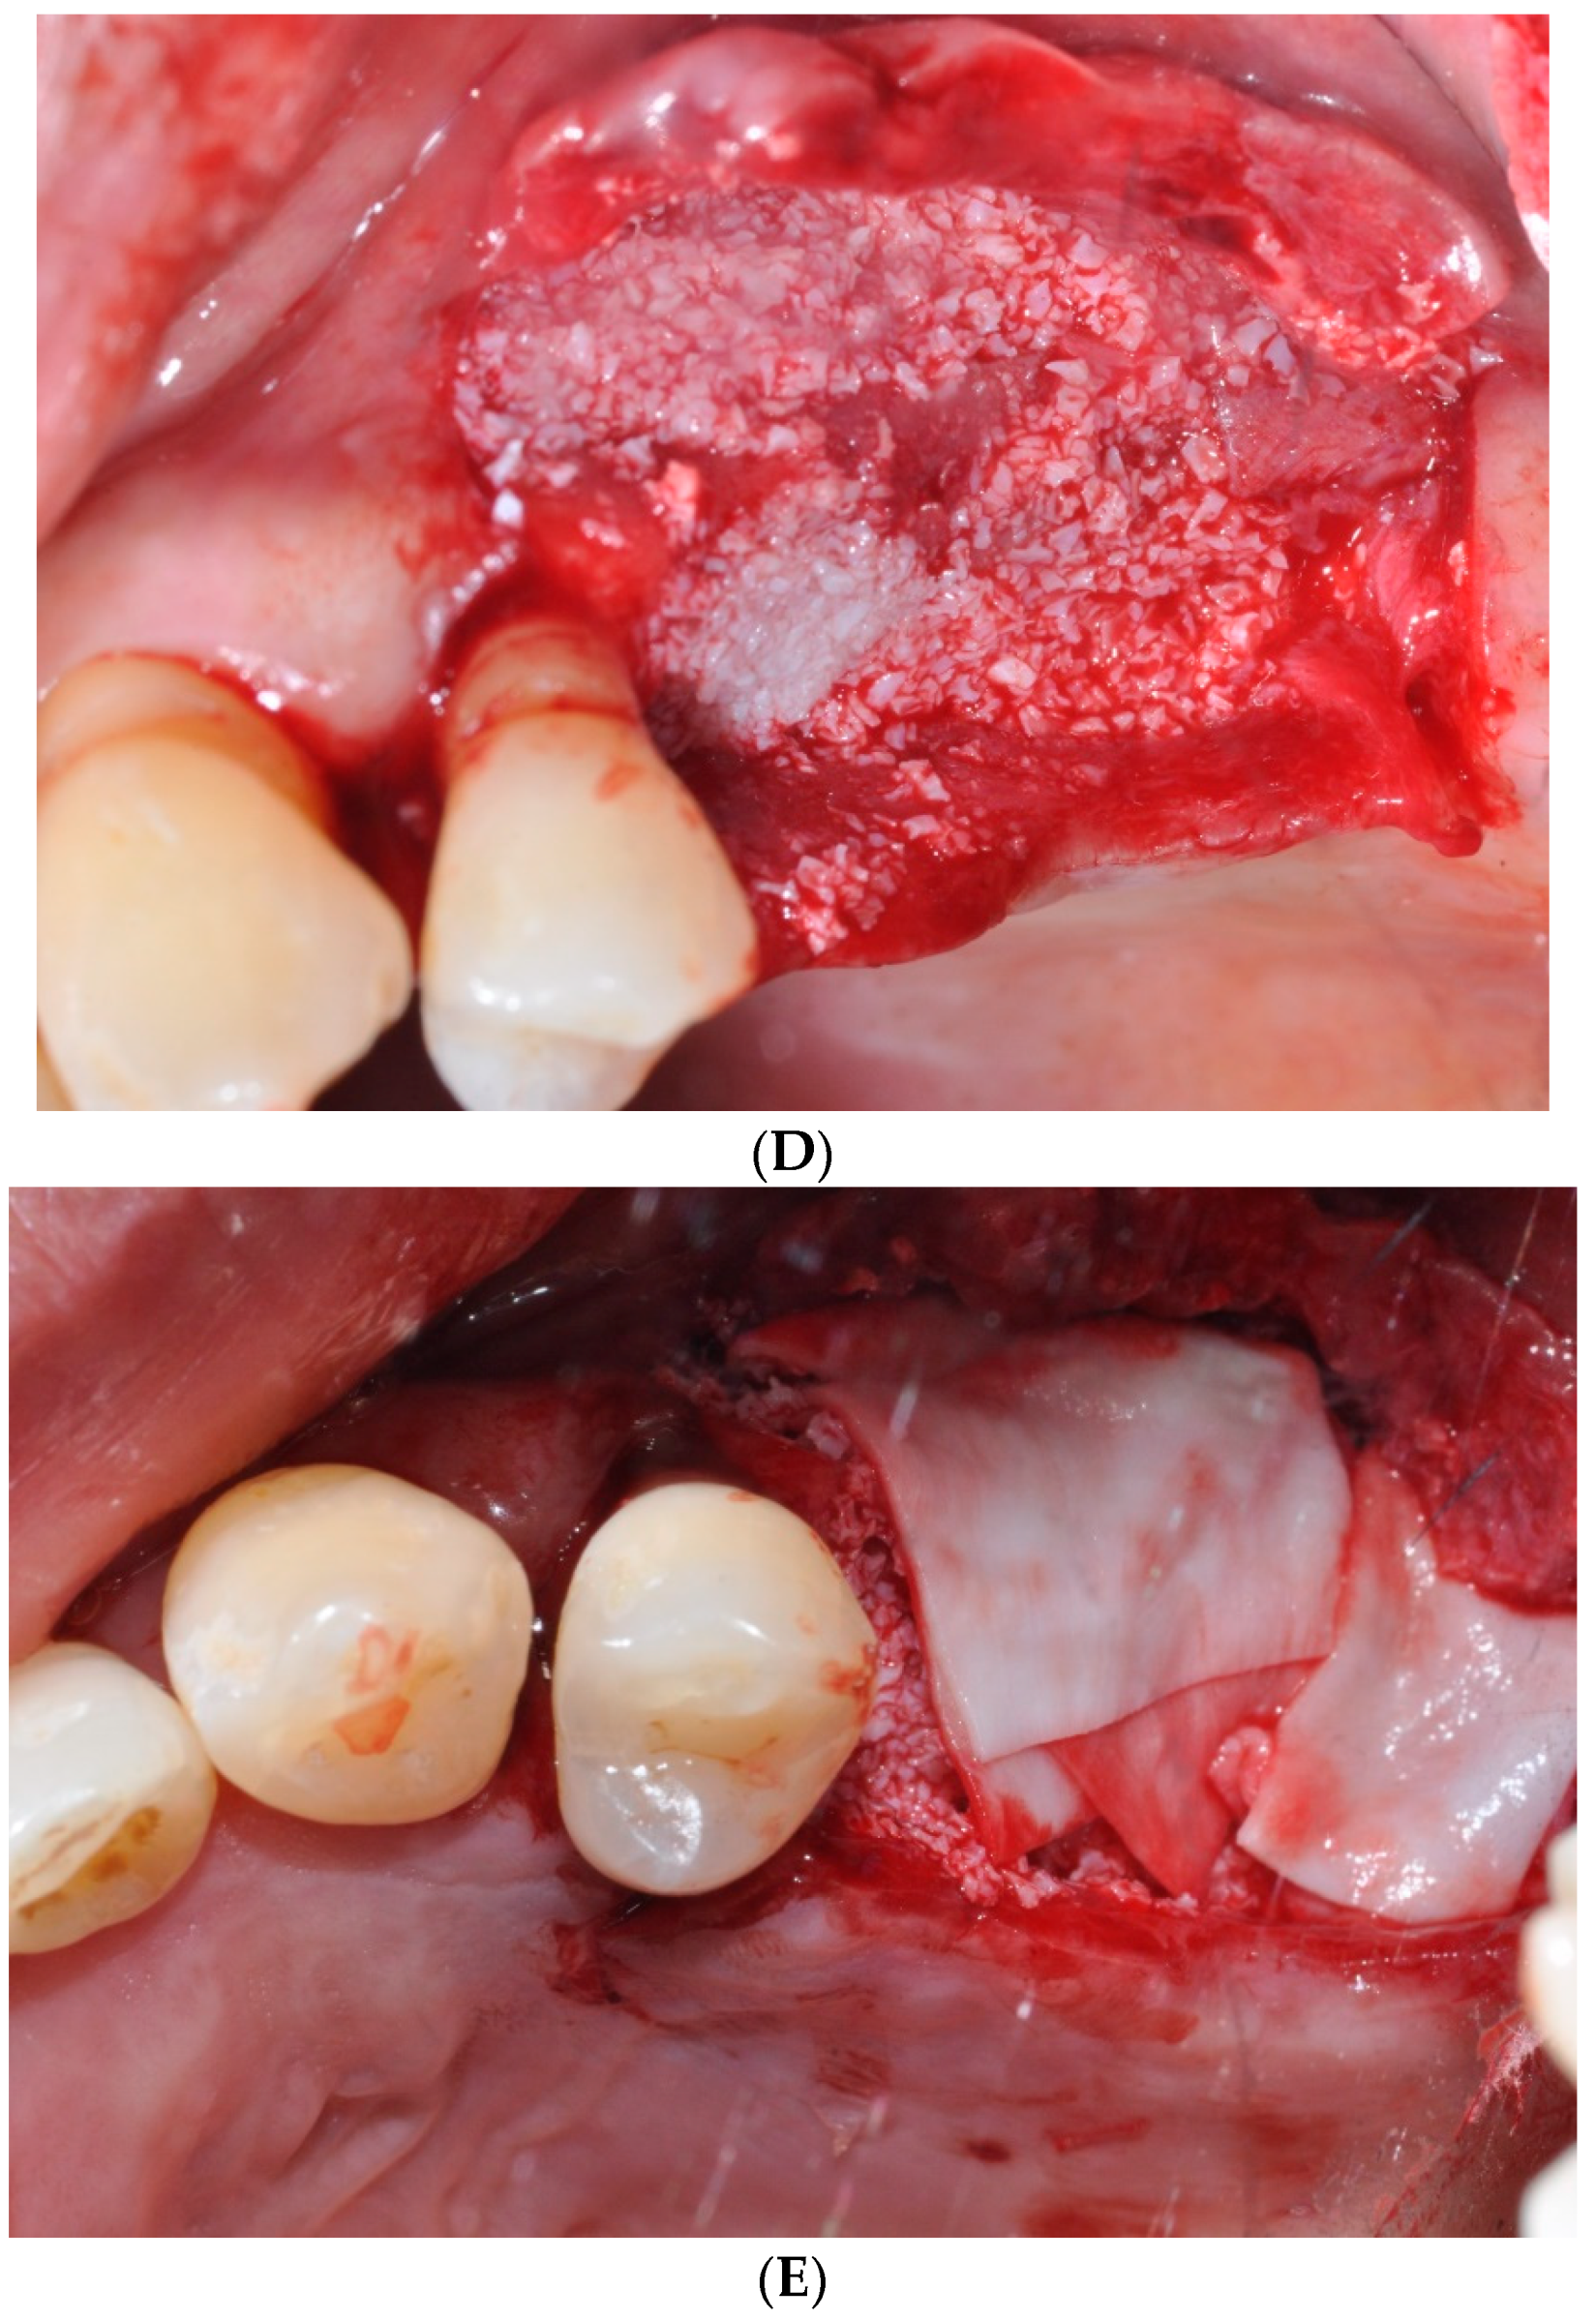

The participants were divided into three groups (sinus augmentation, bone grafting, and no grafting). Three patients each received sinus augmentation, bone grafting, or dental implantation only without sinus augmentation or bone grafting, respectively (Figure 2). The operator carefully elevated the full-thickness flap, gaining access to the surgical site with meticulous precision (Figure 2A). In case of a lateral approach, the low-speed engine with carbide bur with the head size of 0.5–2 mm was used to draw the overall size of the lateral window. Then, the low-speed engine with carbide bur with the head size of 0.5–2 mm was used to make the full cut of the lateral wall (Figure 2B). When the bone cut was fully done, the elevation of the membrane was gently performed with the hand instrument (Figure 2C). This delicate step requires precision and care to avoid any damage to the membrane, ensuring its integrity. The buccal view during this stage showcases the surgeon’s ability to navigate and manipulate the tissue with utmost gentleness, preserving the patient’s sinus health. The sinus membrane along with the bone fragment was elevated, resembling the movement of a trap door, and the void beneath it was then filled with deproteinized bovine bone graft material, specifically Bio-Oss® by Geistlich Pharma in Wolhusen, Switzerland (Figure 2D). Particular attention was given to ensure that the bone graft material was placed adequately on both the mesial and medial sides. Furthermore, extra bone graft material was inserted on both the buccal and palatal sides to expand the width of the ridge. This specialized material is meticulously placed within the sinus cavity to promote new bone growth, providing a stable foundation for future dental implant placement. To protect and stabilize the graft material and facilitate the healing process, a resorbable collagen membrane (BioGide®, Geistlich Pharma) is carefully applied over the augmented area (Figure 2E). This membrane acts as a barrier, preventing unwanted tissue intrusion while encouraging natural tissue regeneration. The clinical view at this stage highlights the placement of the membrane, ensuring optimal results and patient comfort during the healing process.

Figure 2.

Clinical view of the procedure. (A) Buccal view after flap elevation. (B) Clinical view at the time of window preparation. (C) Buccal view following elevation of the maxillary sinus membrane. (D) Sinus augmentation with de-proteinized bovine bone. (E) Application of resorbable collagen membrane.